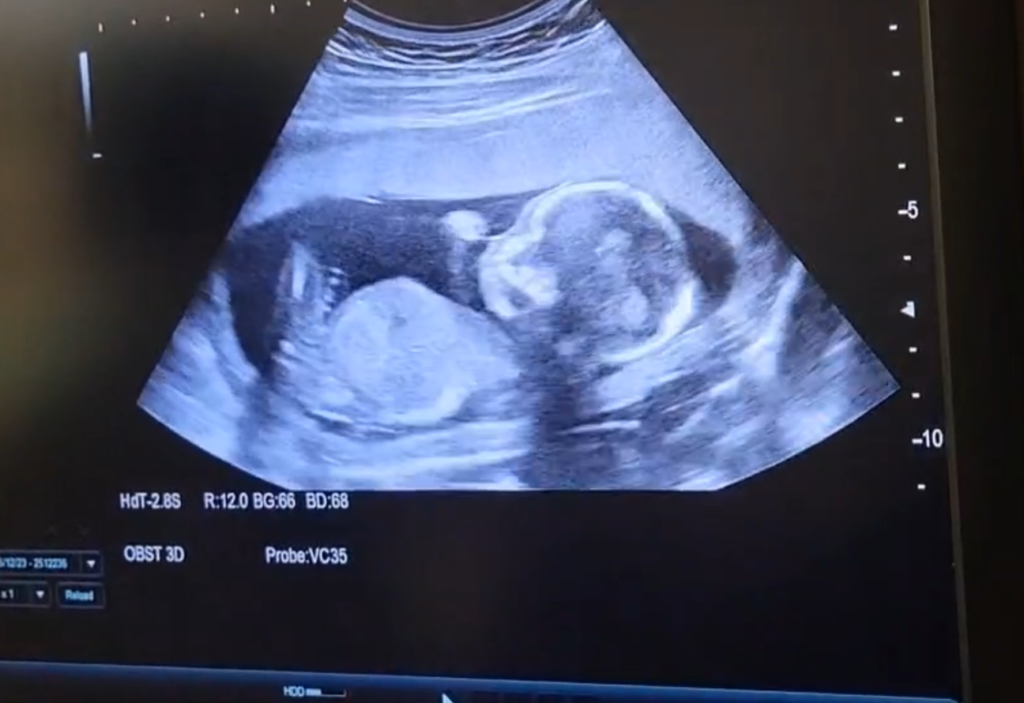

そんなこんなで診察に呼ばれ、3回目のエコー👶

前回のエコーで夫が男の子のアレが見えた気がする…なんて言っていましたが…今回はどうなんでしょうか!

ひとまず赤ちゃんは元気でした🥹

前回とはまた頭の位置が変わってるし、とても大きくなってました><

そしてなんと…まだ16週目ですが性別が判明しました笑

聖母病院のエコーは最寄りの産婦人科でやるよりも結構長めにやってくれたので…性別もなんとなく分かってしまったんです😂

二人でエコー見てたら、なんとなく分かってしまった!!

性別は…

女の子ですっ!!❤️

足の間に何にもなかったので確信しました笑